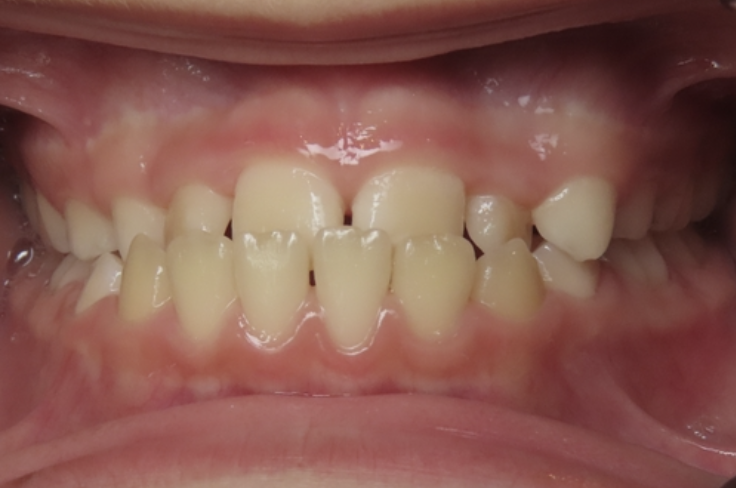

Crowding

Lack of space causes crowding as teeth erupt.